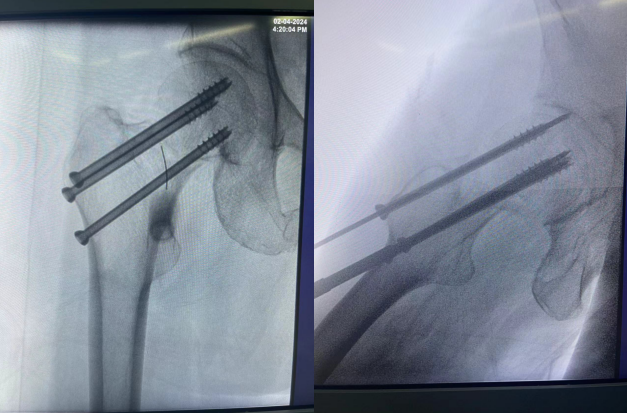

按照术前计划,谢某首先接受了腰麻下的股骨颈骨折闭合复位空心钉内固定术。手术过程非常顺利,四十分钟便完成了。术后观察期间,医生为她进行了精心的后续治疗。病情稳定后,又为谢某做了两次腰椎骨折的微创手术。每次手术过程都是同样短暂,但效果极佳。局部麻醉的运用,谢某在手术过程中几乎感觉不到任何痛苦。

虽然术后的X光片看起来令人触目惊心,但实际上,这些复杂的手术都是通过微小的切口完成的。最大的伤口只有1公分大小,最多只需缝合一针。而背部的切口更是小得如同“小眼”一般,无需缝合和拆线。大约一周后,谢某就可以自行移除纱布了。